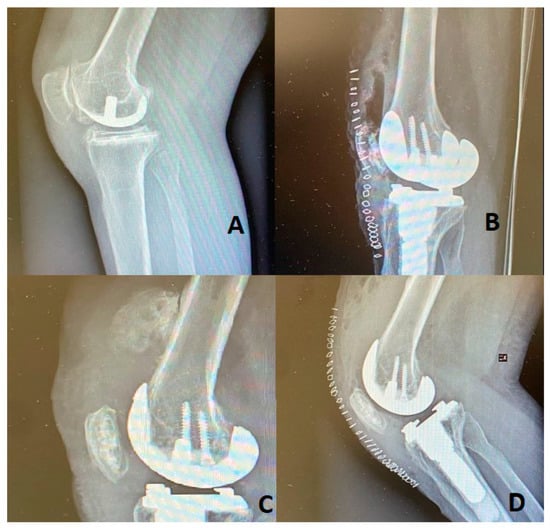

A 42-year-old woman with a Body Mass Index (BMI) of 27.2 and a background of Rheumatoid Arthritis, who had undergone THA 3 years previously (with previous incidences of Heterotopic Ossification treated successfully with radiotherapy) and UKA one year previously, came to our clinic because of a limitation of knee ROM and disabling pain. After an initial visit that included an X-ray, as shown in Figure 1A, a clinical evaluation and clinical tests, including a blood test, were performed to rule out underlying infections. We then decided to revise the UKA with a Cruciate-Retaining Total Knee Arthroplasty (CR-TKA), as shown in Figure 1B.

Figure 1.

(A): UKA radiography of the patient’s knee. (B): X-ray of the Revision of UKA with CR-TKA. (C): Radiography demonstrating the HO. (D): Post operative X-ray after HO removal.

The standard medial para-patellar incision with a mini mid-vastus approach was performed. The surgery was performed by the head of our unit, who is an arthroplasty surgeon with more than fifteen years of experience. The preoperative range of motion in the knee was 10-90 degrees, which was increased to 0-110 degrees postoperatively. The patient underwent postoperative X-ray, as shown in Figure 1B, and rehabilitation consisting of proprioceptive training, neuromuscular reeducation, reinforcement of the thigh muscles, and Continuous Passive Motion (CPM) with a Kinetec device in our clinic. The patient was discharged five days postoperatively. It was not possible to continue the physiotherapy protocol in the outpatient clinic due to the Sars-Cov-2 pandemic, resulting in a failure to regain full extension or flexion of the knee. At the two-month follow-up, the patient came to our clinic with radiography, which demonstrated a large calcification in the distal femoral shaft in the quadriceps expansion as shown in Figure 1C. At that time, ROM was 5–60 degrees. Therefore, we decided to restart physiotherapy. At the six-month follow-up, after three months of physiotherapy, knee ROM was not improving, so it was decided to surgically treat the patient to remove the HO that measured 44 mm, as shown in Figure 2. After the surgical excision, knee ROM was 0–100 degrees. The patient maintained a 0-90-degree ROM and radiography equivalent to the post-surgical that showed no calcifications at the nine-month post-surgery follow-up, as shown in Figure 1D.